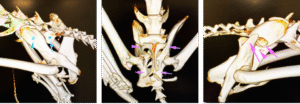

Once stabilised, a conscious full-body CT scan revealed extensive pelvic trauma: a severely displaced left sacroiliac luxation, a right iliac body fracture, multiple pelvic floor fractures, and a left ischial tuberosity fracture for good measure.

Remy’s CT scan